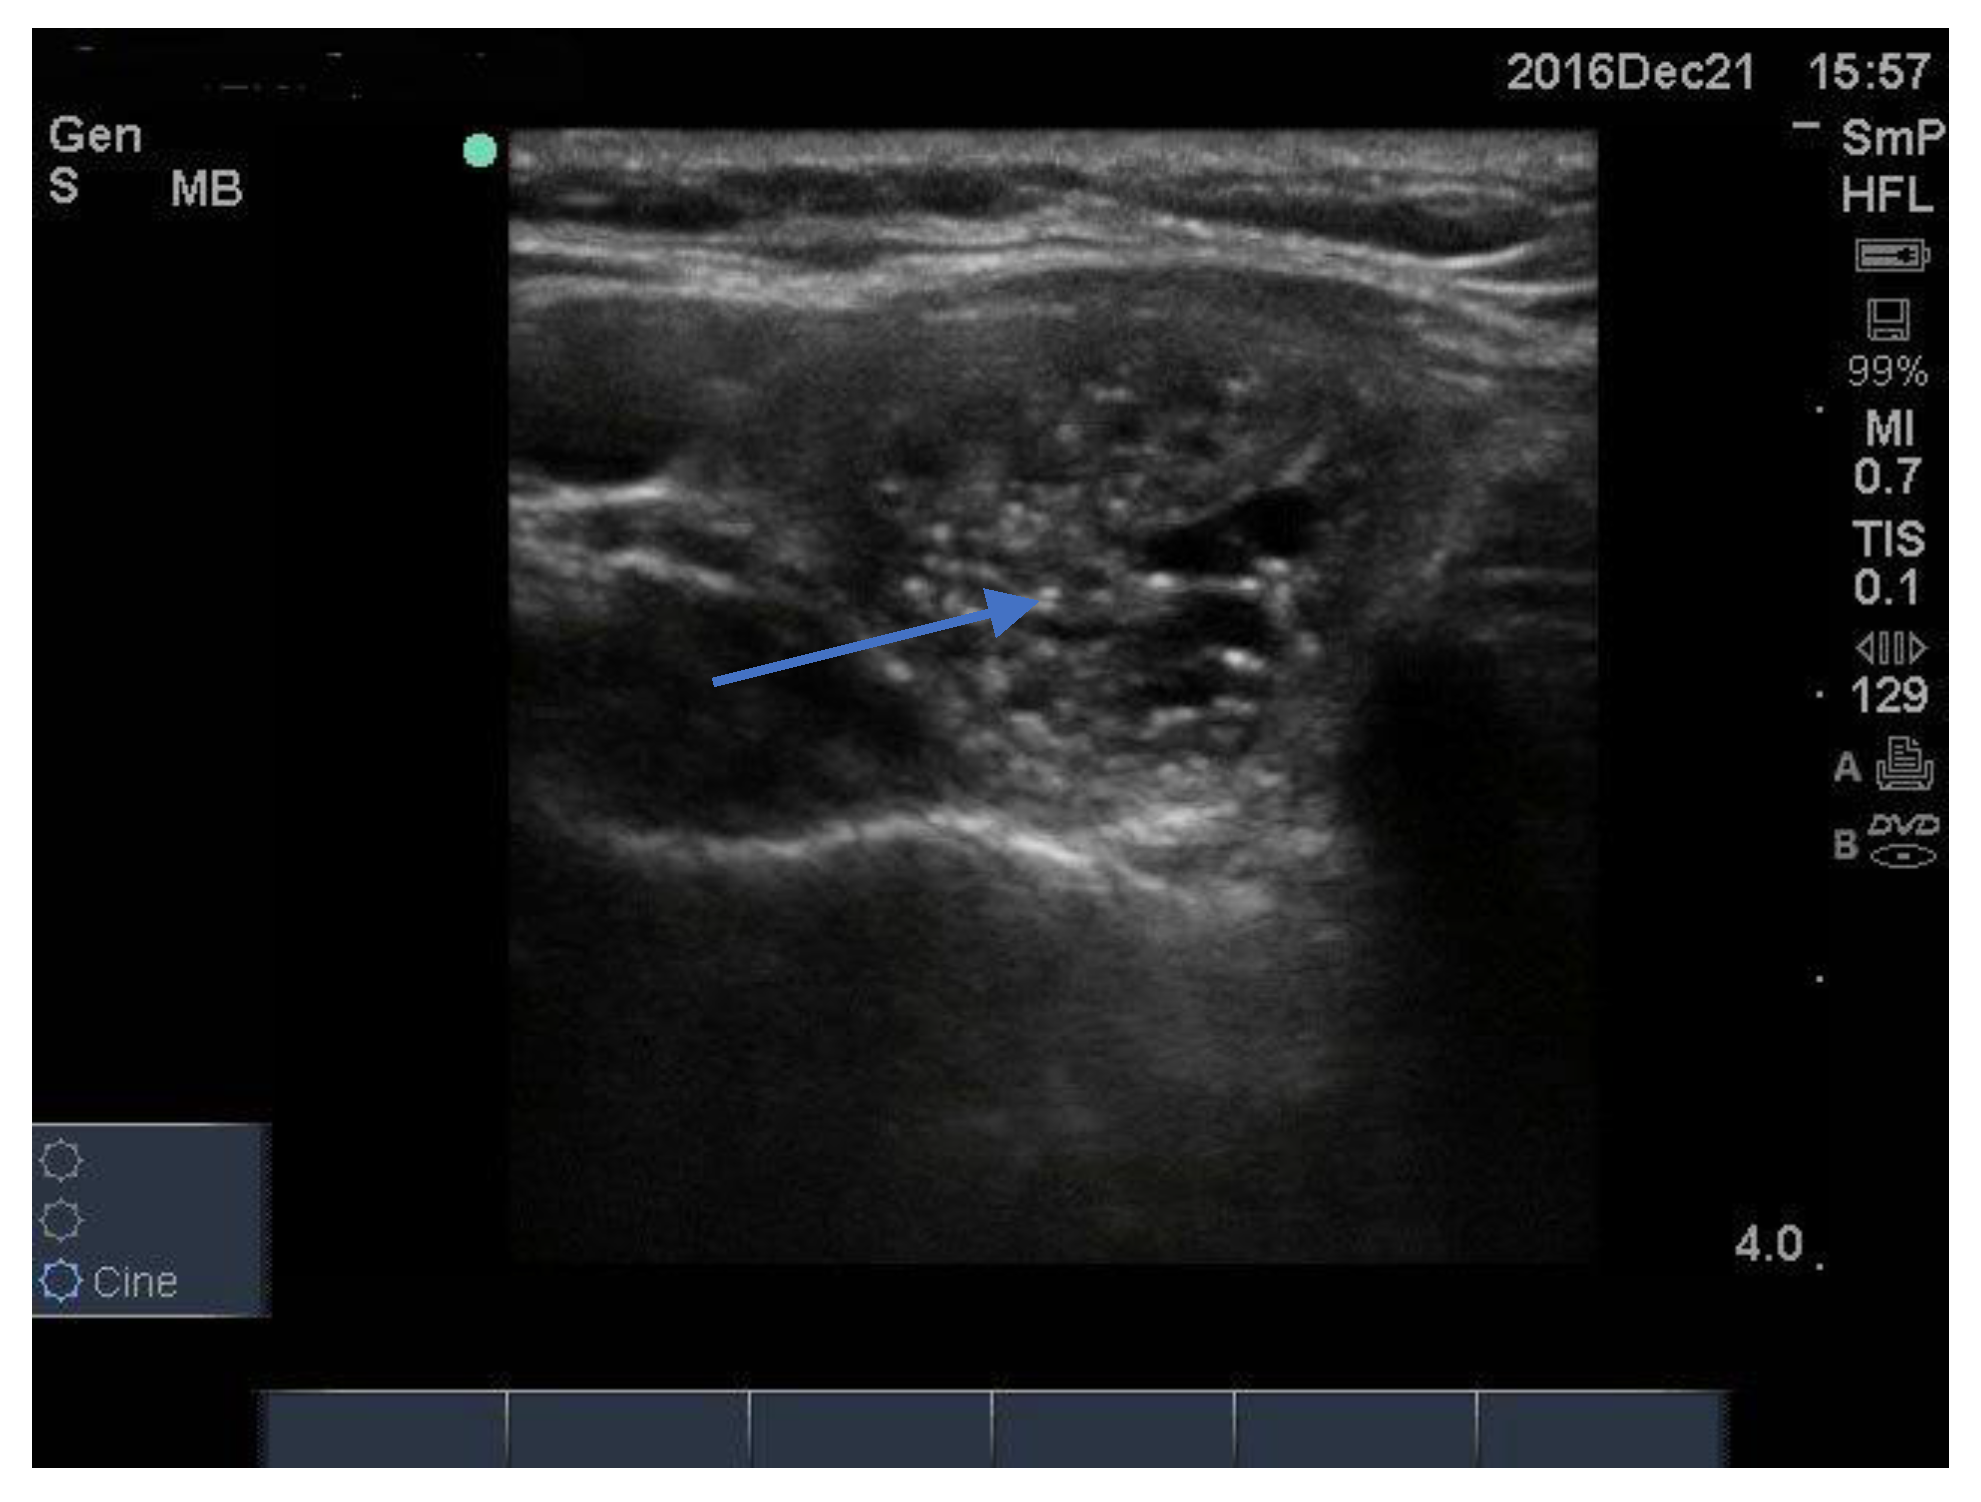

Some intra nodular “microcalcifications” are actually colloid, which may be lined up like a comet tail or dispersed around the inner edge of the nodule (Figure 3). Others, brighter and sharper, are probably colloid crystals. In many nodules there is a single bright spot, often at one side of the nodule, like a nucleus of a cell, that might be the source of the colloid fluid, that could be called a “colloidoma”. Although radiologists describe these as “microcalcifications”—implying suspicion for papillary thyroid cancer—this is probably not correct as, in the authors’ experience, they are quite different from the microcalcifications of papillary thyroid cancer. Finally, some of these colloid bright spots may represent what has been called “the ring down resonance artifact”. Overall, our experience suggests that colloid bright spots are mislabelled as microcalcifications in approximately 30% of cases.

Figure 3.

A benign nodule with a series of bright intramodular microcalcifications (arrow). These spots need to be differentiated from the larger softer (less bright) microcalcifications which are often found in papillary thyroid cancer.